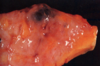

Well-encapsulated fibroadenoma

Cut surface of fibroadenoma

Fibroadenoma with inked surgical margins